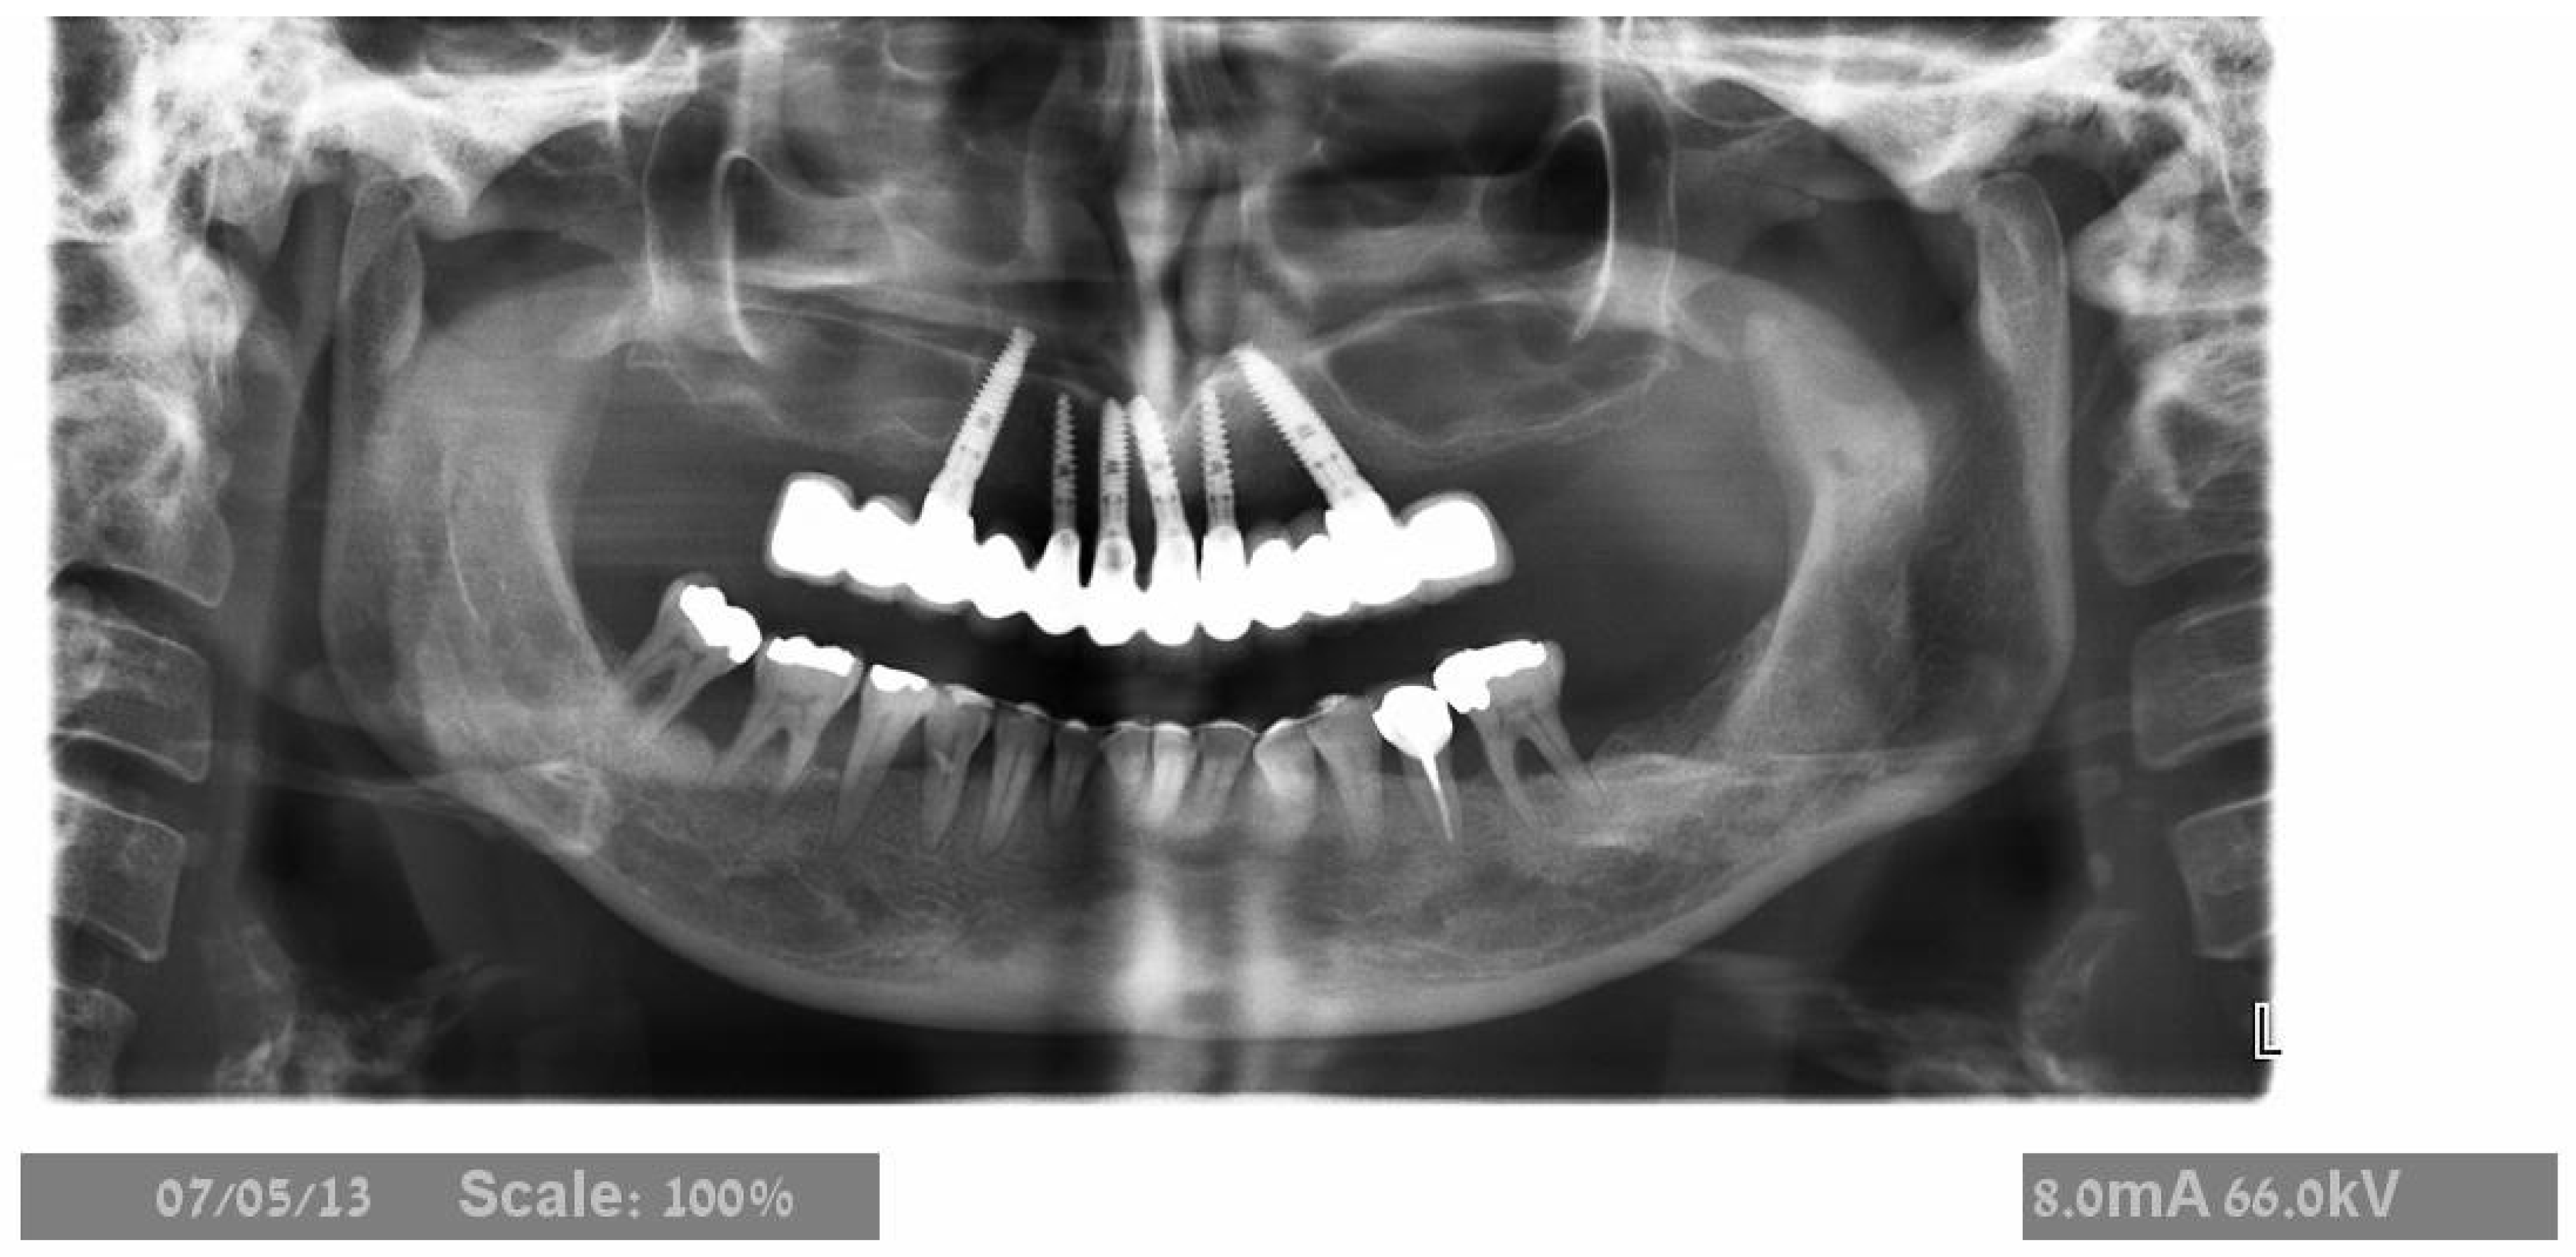

2.2. Surgical Treatment

2.3. Prosthetic Protocol